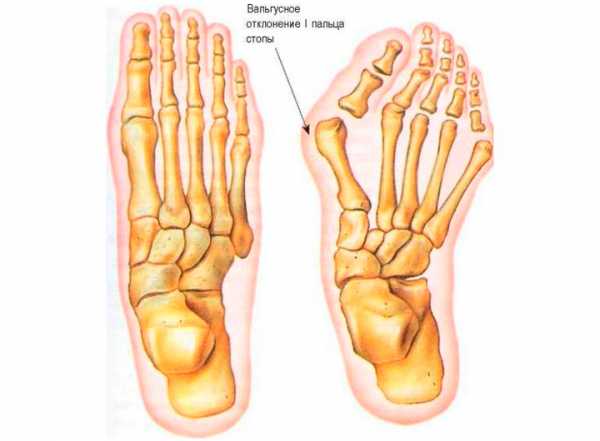

Суть патологии

Вальгусная деформация стопы — патологическое искривление сустава большого пальца внутрь стопы и выход наружу первой плюсневой кости. Из-за этого страдают все остальные костные элементы, связки и сухожилия, поскольку неправильно распределяется нагрузка на ногу.

Помимо этого, есть три стадии вальгусной деформации большого пальца ноги, которые зависят от угла его отклонения:

- Первая стадия – палец отклонен меньше, чем на 20 гр.;

- Вторая стадия – палец отклонен на 25-35 гр.;

- Третья стадия – палец отклонен под углом больше 35 градусов.

Помимо этого вальгусная деформация ступни классифицируется по трем стадиям, которые зависят от угла отклонения:

- Стадия №1 – палец имеет отклонение меньше 20 градусов.

- Стадия №2 – палец имеет отклонение от 25 до 35 градусов.

- Стадия №3 – палец имеет отлокнение больше 35 градусов.